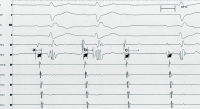

AVNRT - AVB

Abbildung 4: AVNRT- und AVB-II-Mobitz-II: Es zeigt sich eine typische AV-Knoten- Reentry-Tachykardie mit antegrad langsamer Leitung (antegrad slow, lange AH-Zeit [b]), sowie einer retrograd schnelleren Leitung (retrograd fast, kurze HV-Zeit bzw. kurze HA-Zeit [a]). Außerdem zeigen sich auch hier immer wieder spontane infrahisäre AV-Blockierungen (c) (His-Poztenzial)